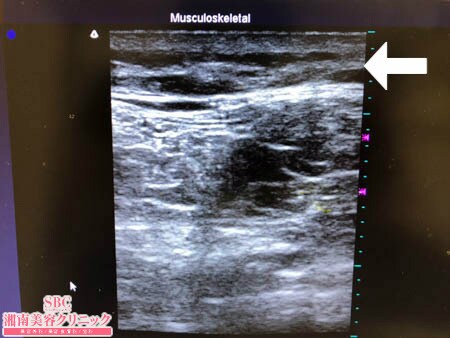

No.202211【脂肪吸引】【動画あり】湘南美容外科全ドクターの脂肪吸引最高責任者である竹田先生による脂肪吸引のフォトギャラリー!ただただ細くなりたいんです!という患者様の太ももの脂肪吸引!術中3Dタッチビュー・右太もも後面

画像上でも明らかなように

徹底的に根こそぎ!!

ましたので術直後の皮下脂肪層は

極限まで薄くなっています。